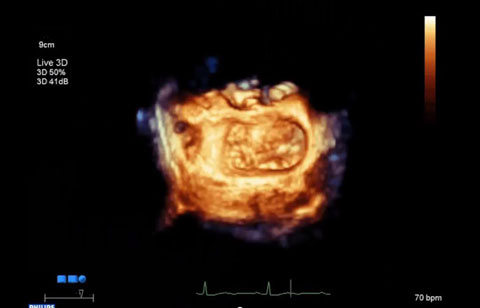

قد تساعدك صور Live 3D TEE الديناميكية في تحديد مدى تأهل المريض للخضوع إلى عملية إصلاح الصمام الميترالي باستخدام القسطرة، كما تقدم توجيهًا أساسيًا في الفترة المحيطة بالإجراء، بدءًا من اكتشاف الثقب الخطر عبر الحاجز ووصولاً إلى عرض الجهاز والتقييم الذي يلي مرحلة الاستخدام.